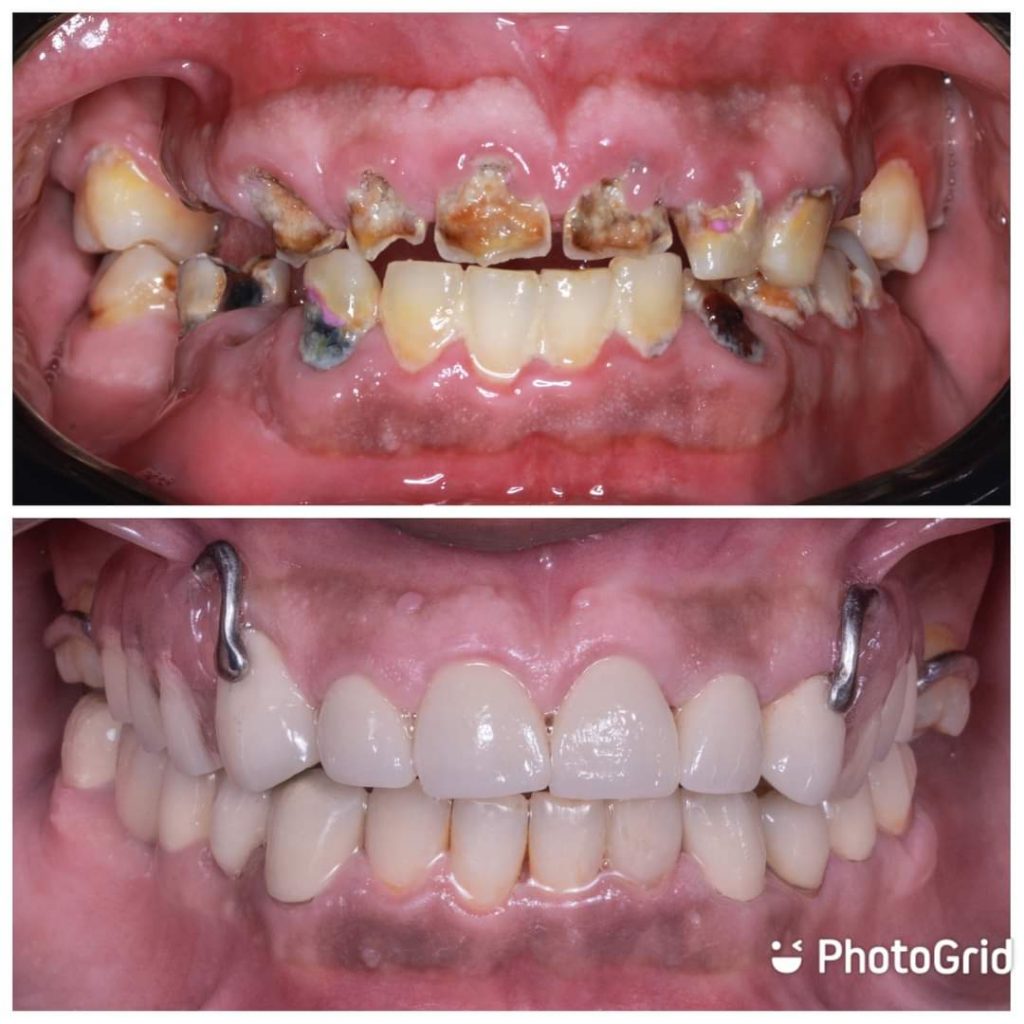

Hi this is my first full mouth rehabilitation case as graduation project .

In this case , I start extra-oral analysis to determine ricketts angle plane for maxillary anterior crowns protrusion to overcome crossbite.

Serial extraction for hopeless teeth no 18,15..24,25,28 also, teeth no 37,44

Surpa/ sub- gingival scalling

Next visit curettage to eliminating pockets lining epithelium and periodontal pack was placed to promote healing process ( removed after 10 days and measuring probing depth again for re-evaluation)

Excavation for all caries lesion to stop carious process .

After, proper diagnosis,radiographic and clinical examination , endodontic treatment was done for teeth no 13,12,11..21,22 also, teeth no 33, 34,36

PFM crowns on 13,12,11,21,22,23,33,34,35,36

Metallic RPD done on surveyed crowns no.13,17… 23,27

Aker claps on 17,27

Cingulum rest seat and RPI clasp on surveyed crowns